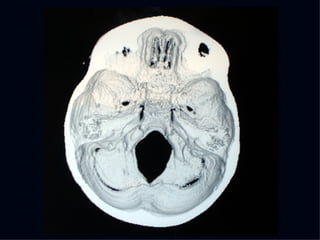

The document discusses the contributions of various figures in the field of medical imaging, including Wilhelm Röntgen and his discovery of X-rays, and the development of CT imaging and MRI technology. It highlights the historical significance of early imaging techniques and the initial skepticism from medical professionals regarding their usefulness. Key milestones in imaging are noted, along with the eventual acceptance of such technologies in clinical practice.